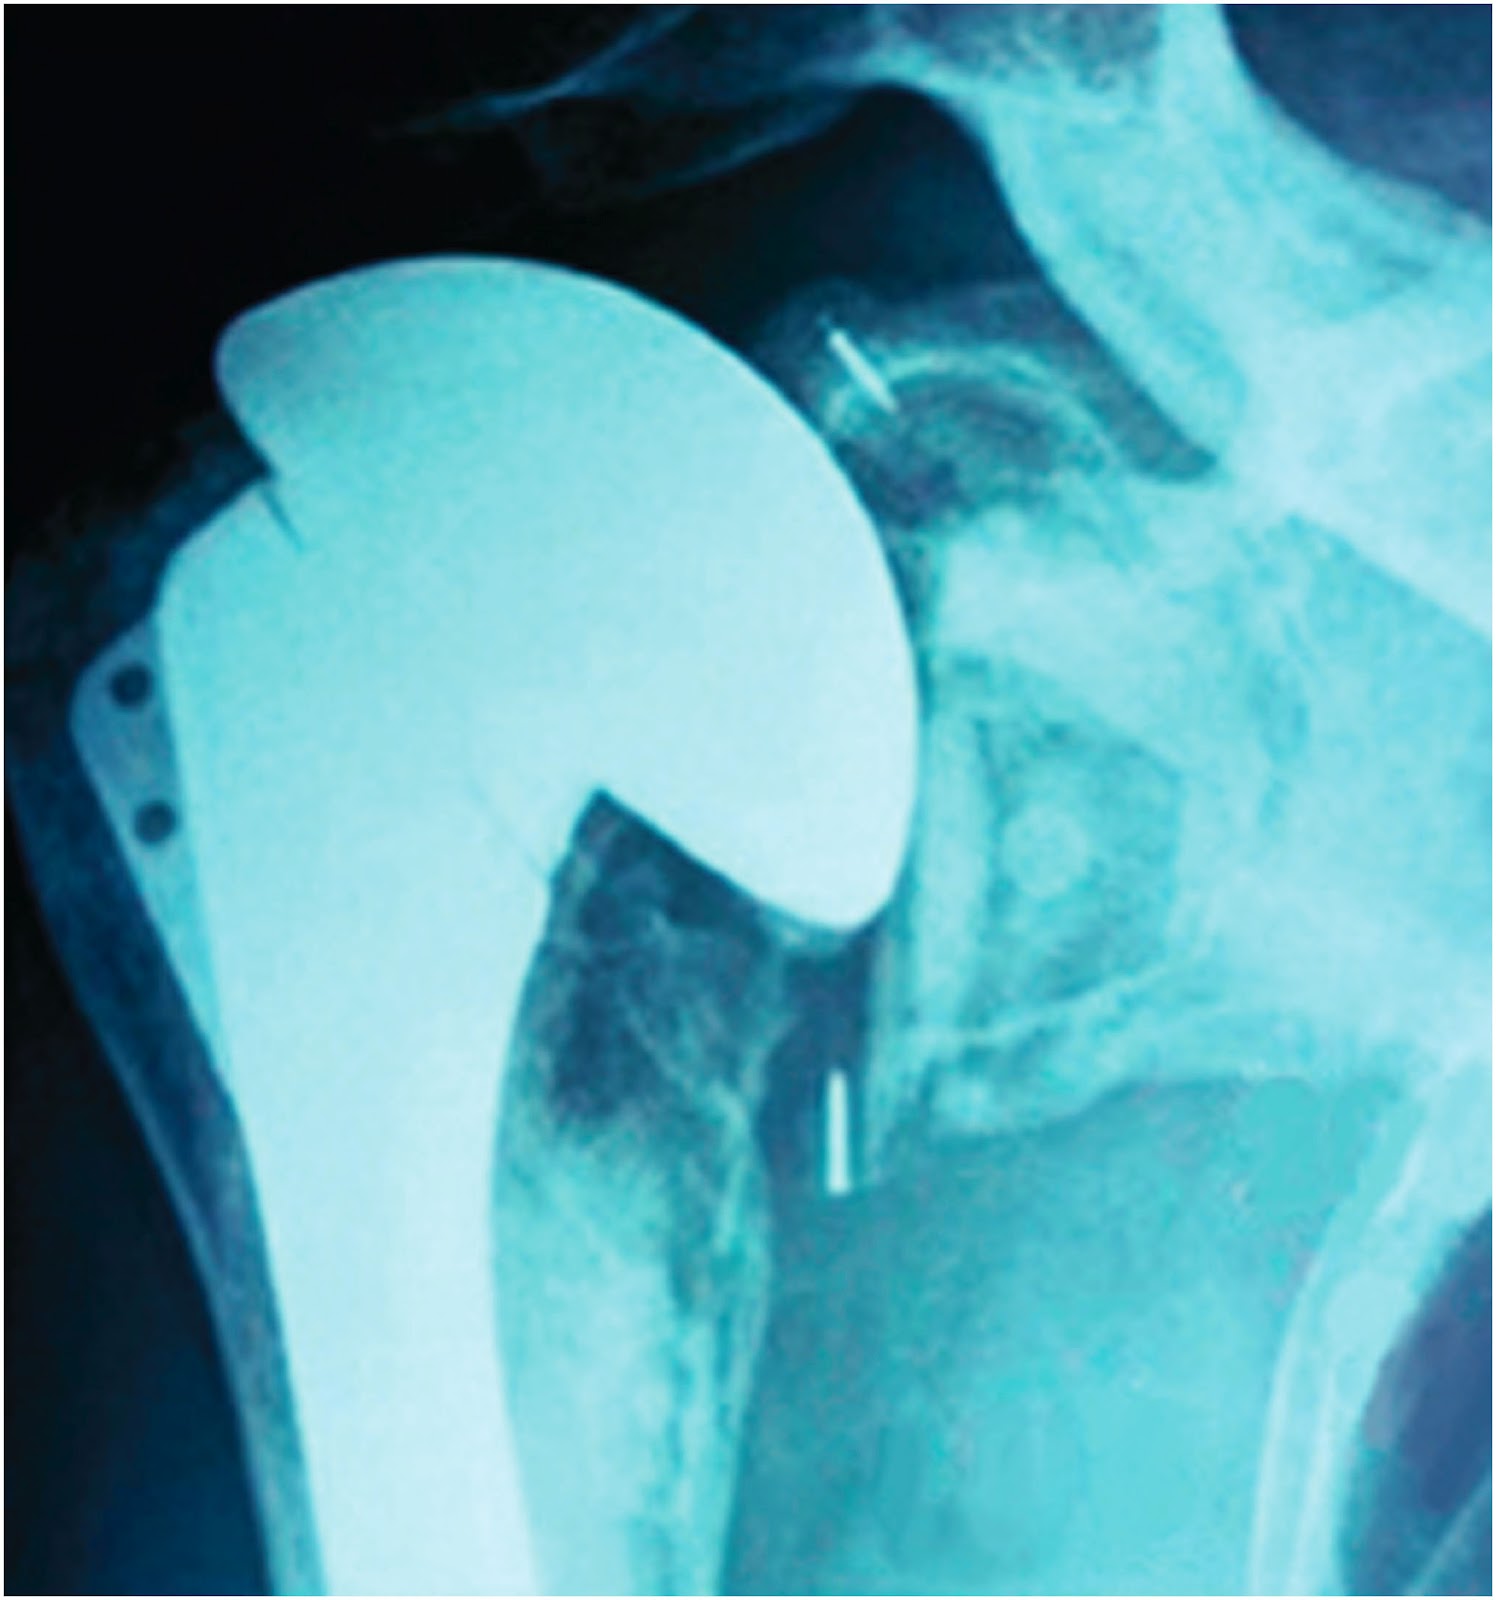

“infection after reverse shoulder arthroplasty: There has yet to be a consensus on the optimal treatment for periprosthetic infection after shoulder arthroplasty, and most treatment is based upon surgeons’ past clinical experiences and use of data from infection treatment following hip and knee arthroplasty. If you suffer a surgical infection following a procedure, there may be any number of causes.

Although indolent in its growth and presentation, infection of the shoulder with p acnes can have devastating effects, including failure of the surgical intervention. Infection is a significant complication after shoulder arthroscopy and shoulder arthroplasty that can lead to significant morbidity. Burkhead is a renowned orthopedic and shoulder surgeon.

Any infection carries risks, and can also jeopardize positive surgery outcomes. Despite the innovation and success of modern arthroscopic and open shoulder surgery, postoperative infection remains a burden to both the patient and surgeon. There is special emphasis on indolent infections related to propionibacterium acnes and the challenges associated with the diagnosis and management of this pathogen.